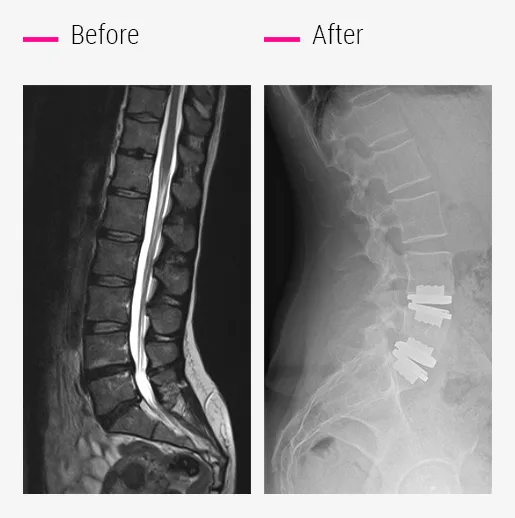

What to do about recurrent herniation?

These symptoms sometimes occur in people who have undergone discectomy surgery for one or more herniated discs.

It is important to understand that the purpose of a discectomy is to relieve the compression of the nerve by disc fragment ejected from its housing, but it does not treat the disc disease responsible for the herniation, which will continue to progress.

- Prodisc-L® total disc replacement treats the diseased disc and the hernia in a single operation.